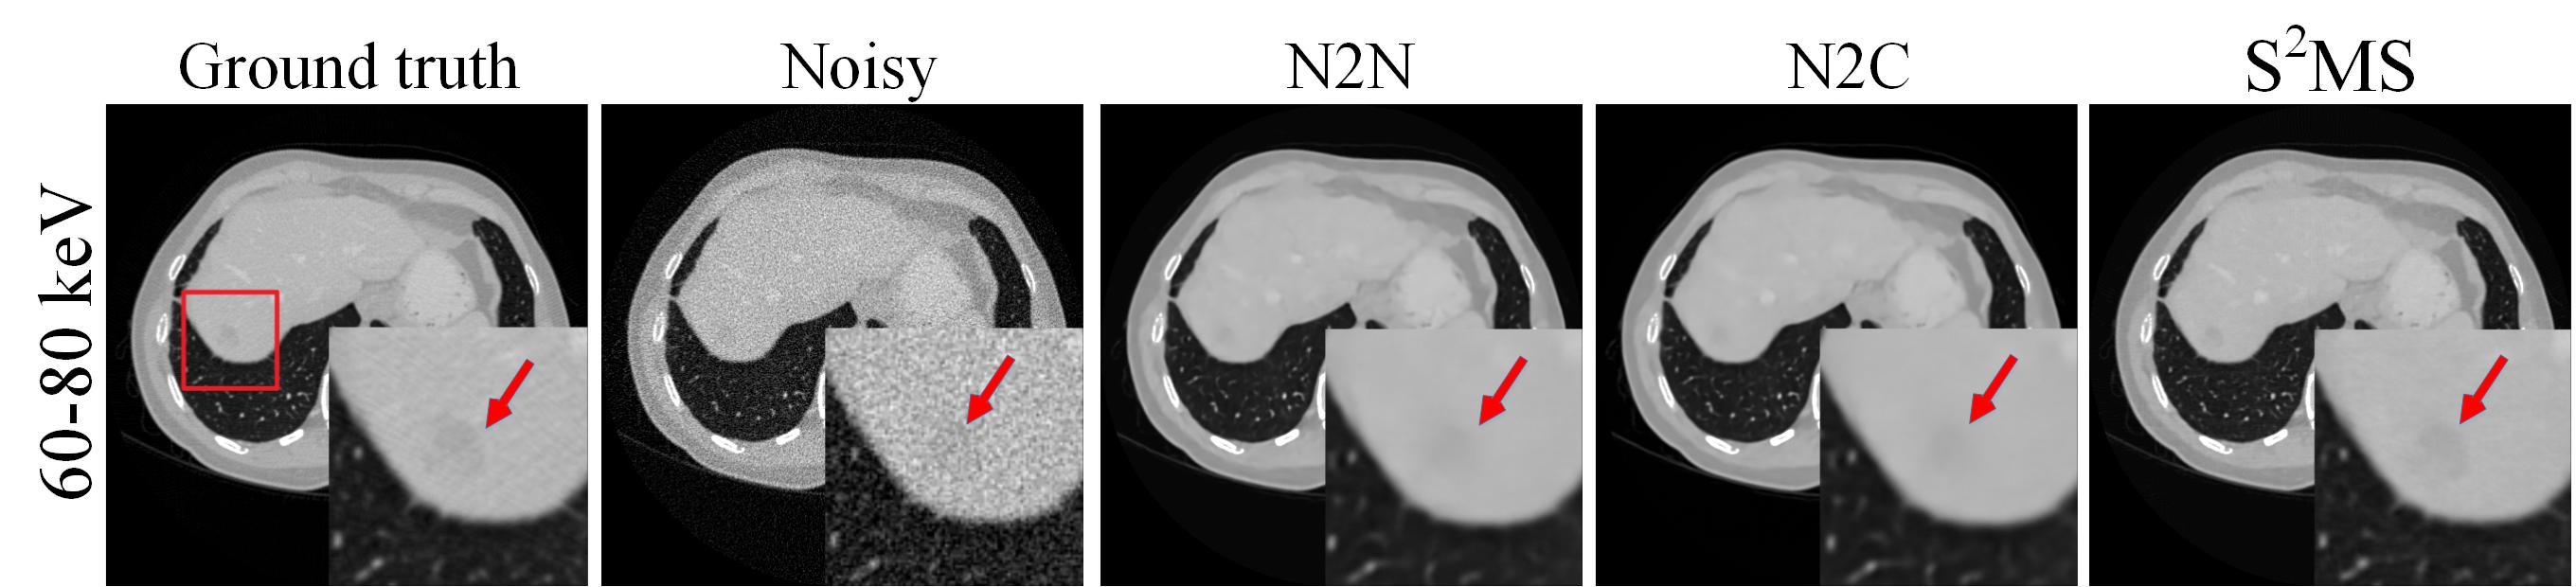

Figure 6: A reconstructed PCCT image in channel 3, the noisy image and the outputs of different network. The shading in the red rectangle is the region of lesion which is magnified and shown. The display window is [0,0.35] cm-1.

To further validate the performance of the proposed method in PCCT clinical application, CT images with lesion is shown in Fig. 6. Denoised reconstructed images in channel 3 (60-80 keV) of different methods are illustrated and the lesion region (red arrow) is magnified. The lesion is hardly observed in the noisy image while it can be clearly in the reconstructed image by S2MS. The lesion area was blurred in the reconstructed images denoised by other methods. This result indicated that our method has potential in clinical application.